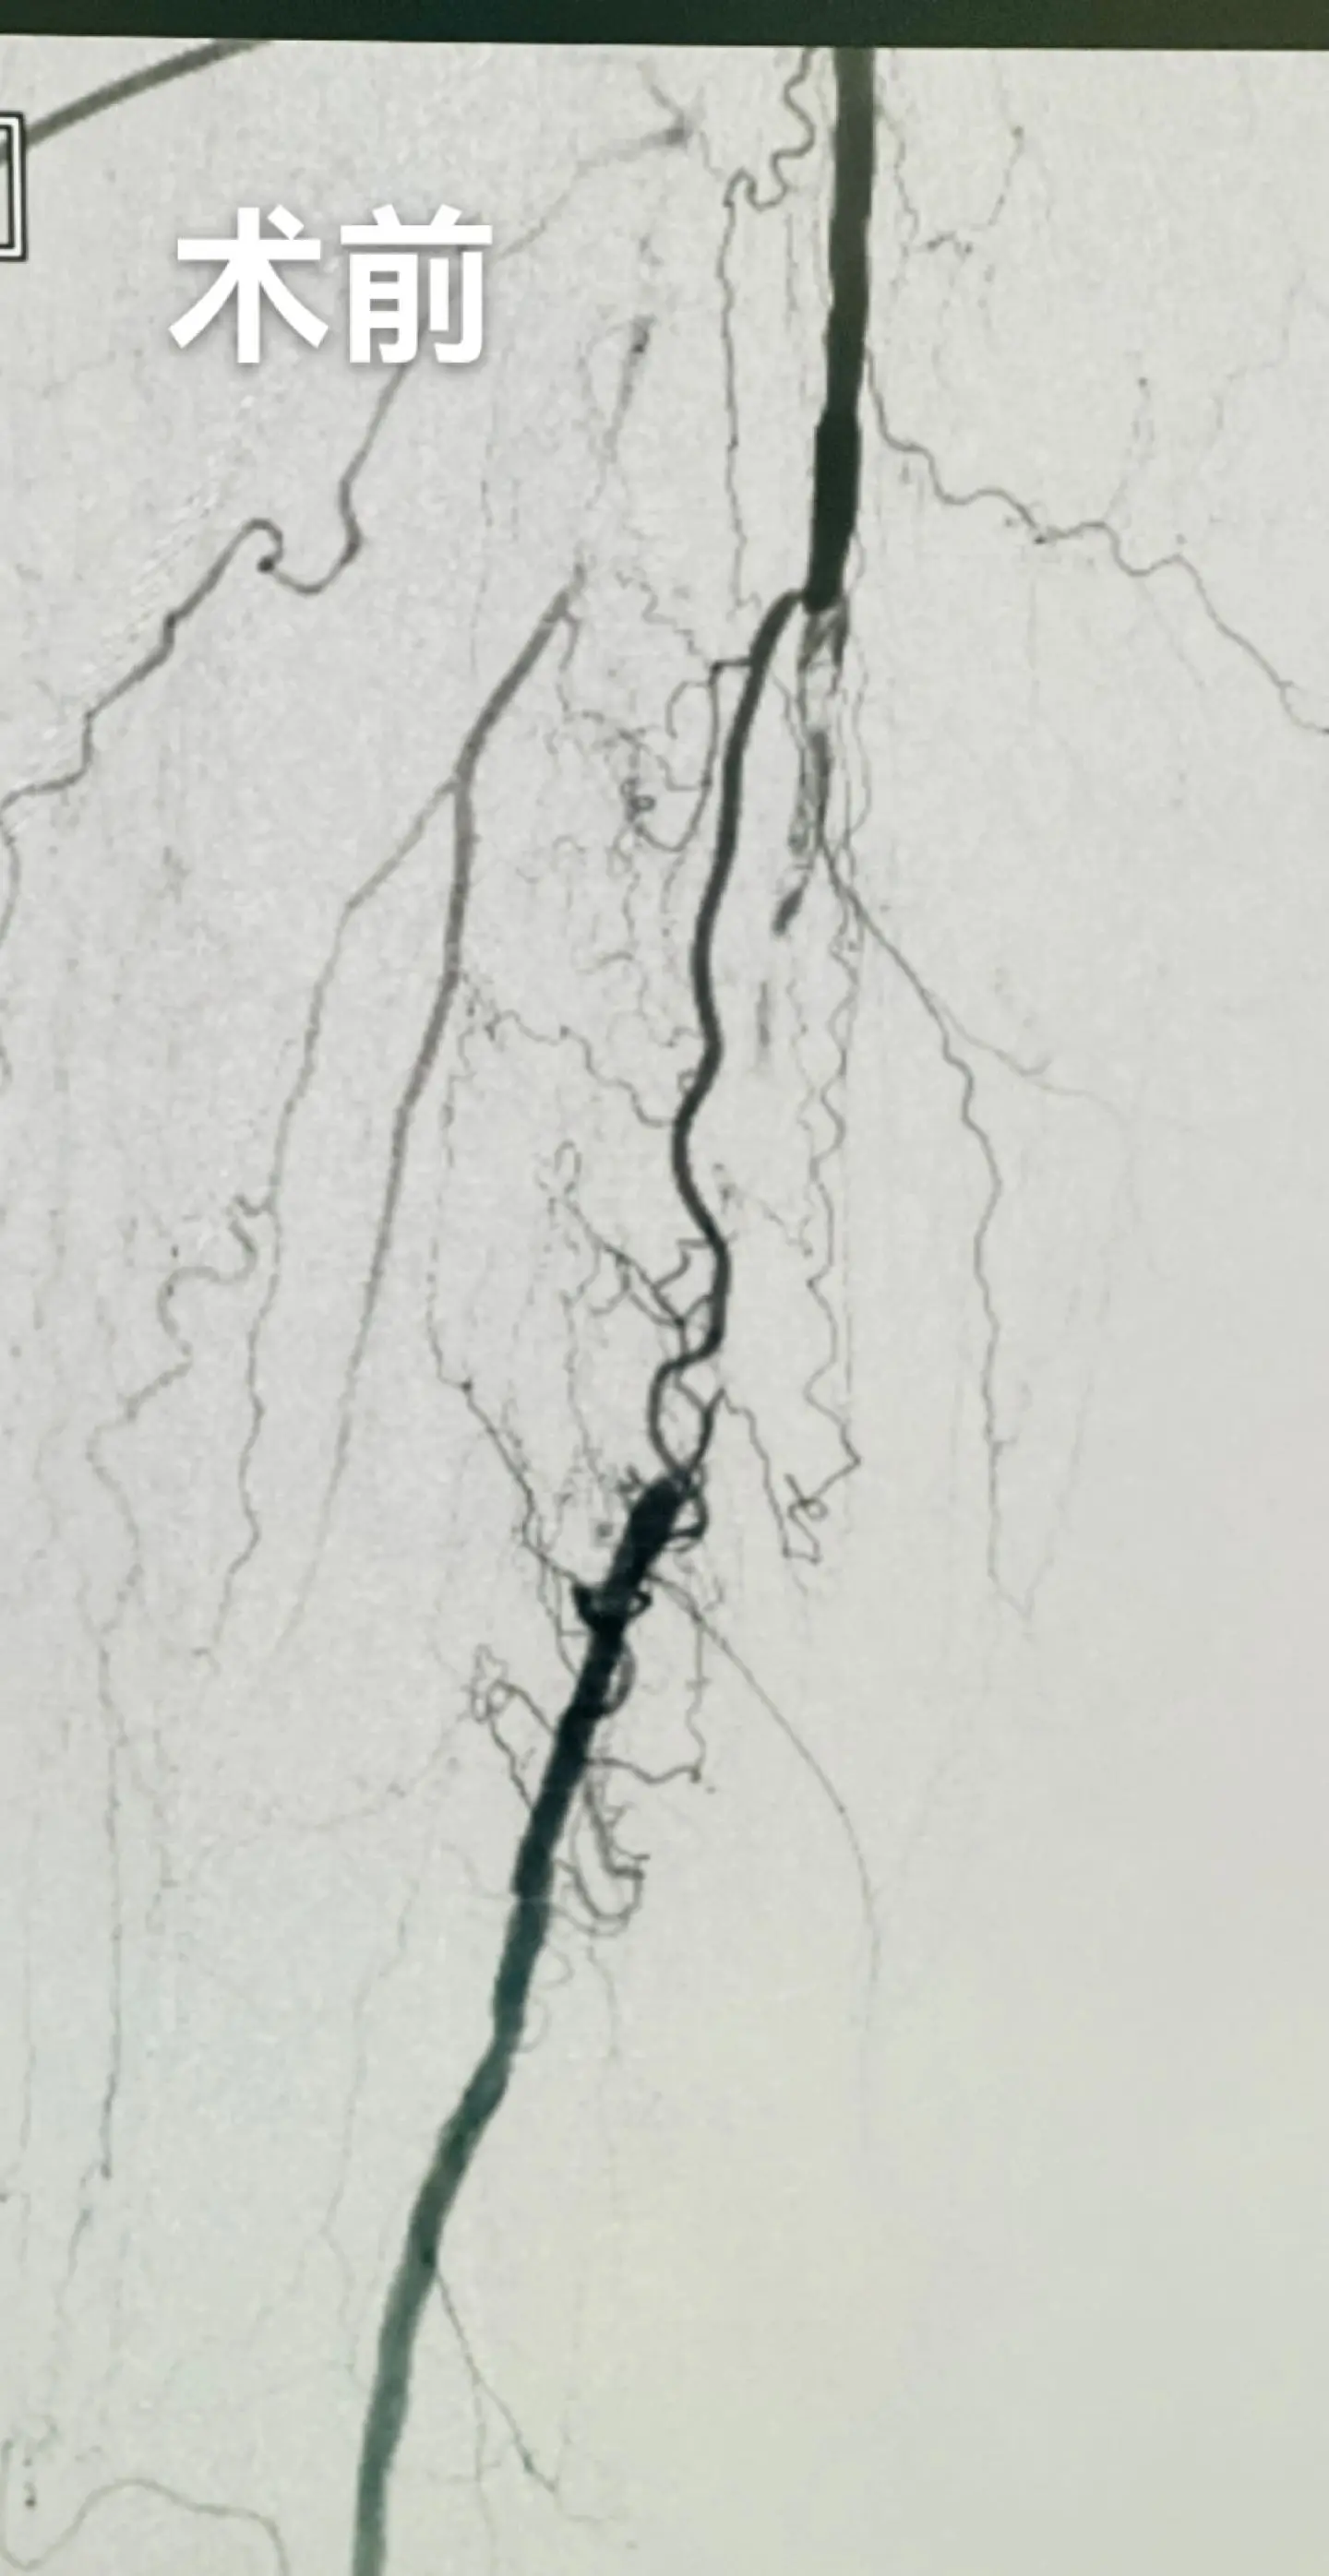

入组本中心首例外周药物涂层支架,为患者减免了约3W的耗材费用

糖尿病足,反复下肢溃疡,膝下三条血管全部开通,保证血流,促进创面愈合